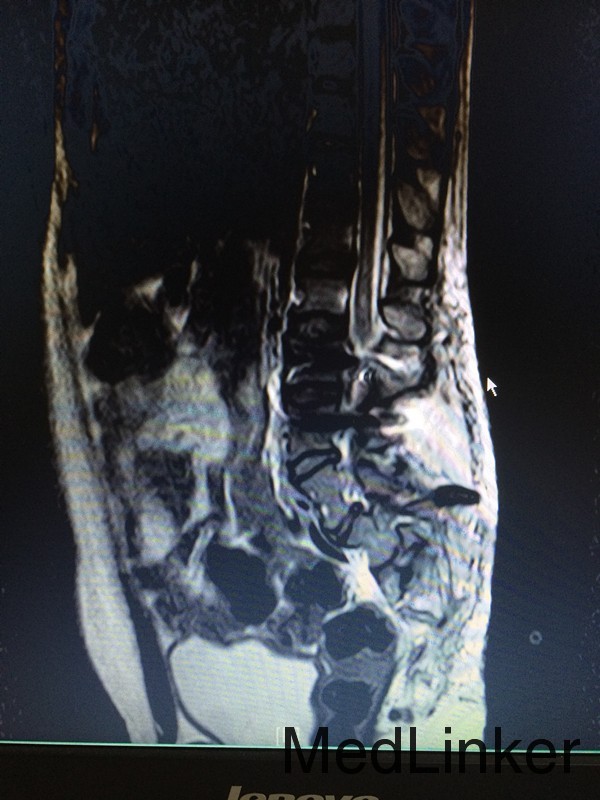

查体:腰椎后突畸形,双小腿肌肉萎缩,双足内翻畸形,双侧踇指伸指无力。 辅助检查:行脊椎MR检查提示:骶椎发育畸形,脊髓圆锥低位,考虑脊髓栓系综合症,神经源性膀胱。

诊断:脊髓栓系综合症 治疗:神经外科联合骨科在全麻下行脊髓栓系松解、椎板修补术,术后予对症支持治疗。